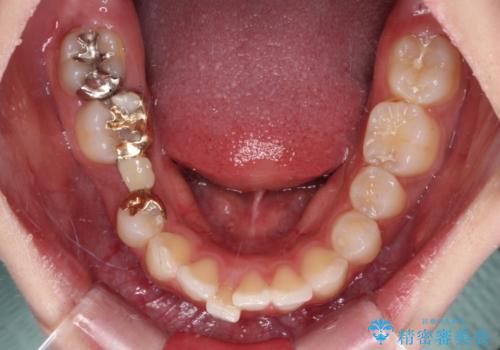

- 上の前歯が下唇に当たる感覚と奥歯の欠損を気にして来院された患者様です。

後方移動と同時上下歯列をワイヤー装置にて整え、奥歯の欠損部には矯正治療の途中でインプランを埋入していくこととしました。

上顎歯列全体を後方移動させたことで唇に当たる感覚は改善され、更には上下の正中位置も合わせることができました。